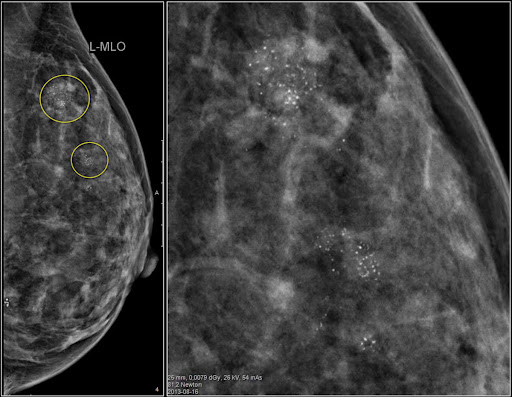

Як і при звичайній мамографії, на зображенні жирова тканина виглядатиме темною, а ділянки грудей із залозистою, фіброзною тканиною і новоутворення (якщо вони там є) будуть світлими. Відмінність полягає лише у тому, що на знімках прицільної мамографії буде зображена саме та ділянка, яка зацікавила лікаря з приводу можливої присутності новоутворення, а не вся молочна залоза.

Сучасні мамографи дозволяють отримати високоточне цифрове зображення, за допомогою якого можна виявити новоутворення дуже малих розмірів, від 0,2 мм. І це так важливо для ранньої діагностики злоякісних пухлин на початковій стадії розвитку, коли вони не викликають симптомів і не відчутні при пальпації грудей.